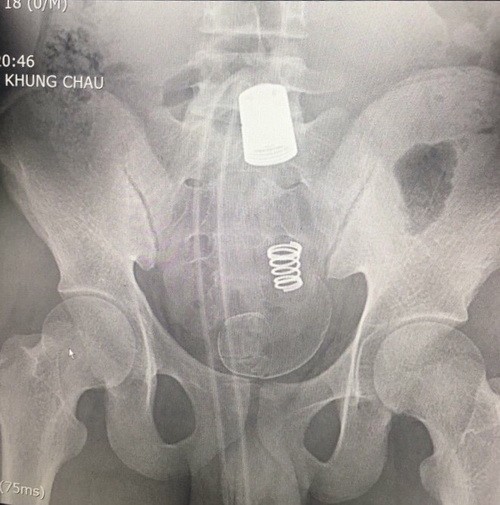

Dị vật bị mắc kẹt trong hậu môn bệnh nhân trong phim chụp X.Quang - Ảnh: VTC

Theo thông tin từ báo Người Lao Động, vừa qua các bác sĩ Khoa Ngoại tiêu hóa - tổng hợp, Bệnh viện đa khoa tỉnh Hải Dương đã phẫu thuật thành công cho một trường hợp bệnh nhân nam 18 tuổi ở Hải Dương bị dị vật là chiếc vòi của bồn vệ sinh mắc ở đại trực tràng.

Theo lời bệnh nhân, trong lúc bệnh nhân đi đại tiện và sử dụng vòi xịt vệ sinh xịt rửa phần hậu môn. Do hậu môn co thắt nên đã làm vòi xịt chui sâu vào hậu môn, không thể kéo ra được. Bệnh nhân đã dùng dao cắt rời đoạn vòi nước và đến bệnh viện cầu cứu bác sĩ.

Chia sẻ với báo VietNamNet, BS Trần Văn Minh, khoa Ngoại Tiêu hoá – Tổng hợp cho biết, do phần dị vật nằm rất chắc, không thể rút ra qua đường hậu môn, xuất hiện chảy máu niêm mạc ruột, nên buộc phải mổ cấp cứu.

Ekip phẫu thuật khoa Ngoại tiêu hoá đã phẫu thuật mở bụng, mở đại tràng sigma lấy được cả đoạn vòi nước và đầu xả dài khoảng 45 cm.

Dị vật gây tổn thương niêm mạc ruột, do đó bác sĩ phải đưa đại tràng sigma ra ngoài làm hậu môn nhân tạo và dự kiến sẽ lập lại lưu thông ruột (nối lại ruột) khi đủ điều kiện. Sau 10 ngày điều trị tại BV, hiện nam bệnh nhân đã được xuất viện.